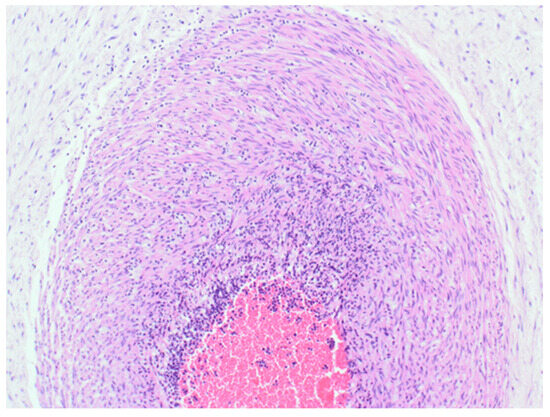

Figure 4.

Haematoxylin & Eosin (200×). Part of the cross section of the umbilical cord, showing transmural acute inflammatory cell infiltration of the vessel wall consistent with funisitis.